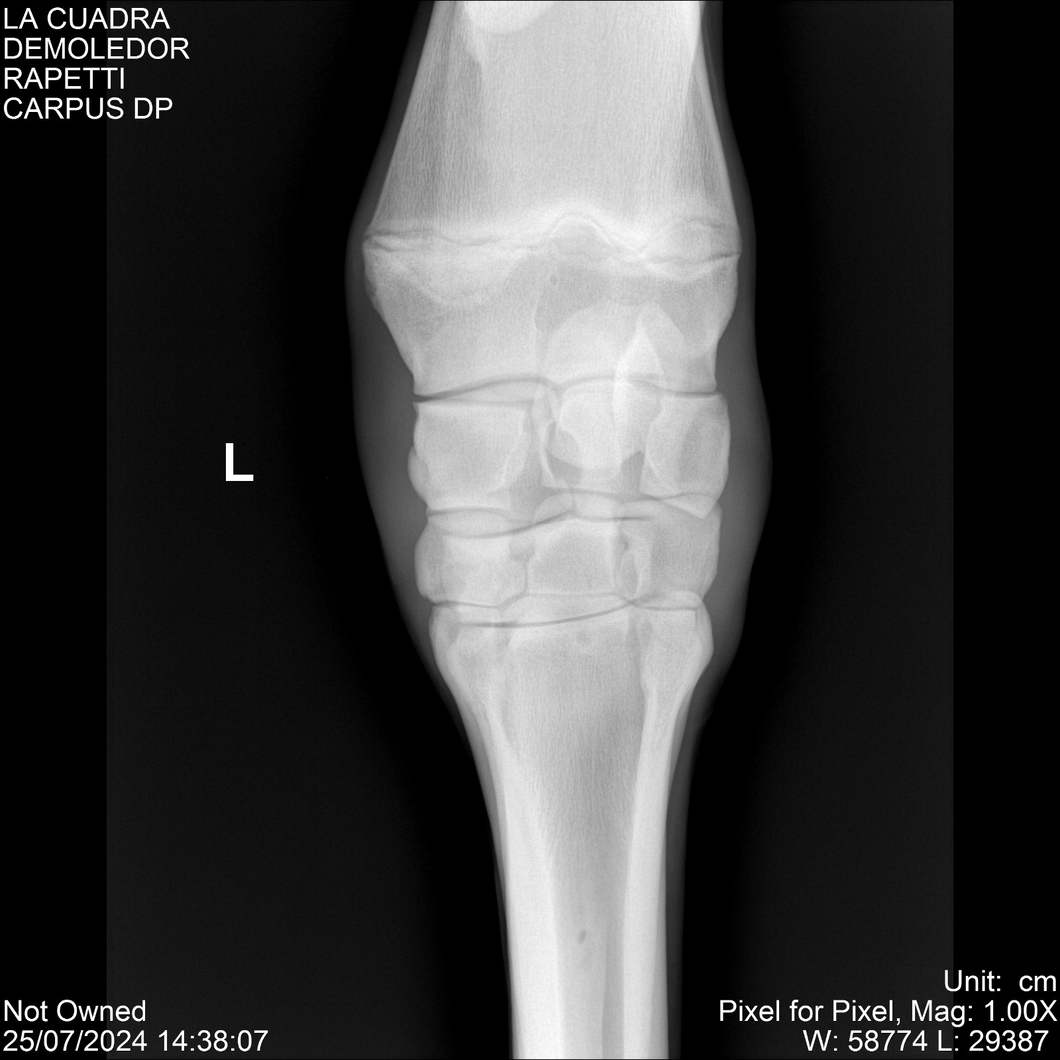

LOTE 14, DEMOLEDOR 🔥 🔥 🔥 Lote Anterior Volver al remate Lote Siguiente Ficha Contacto Montevideo - Ficha del Lote Identificador: #284454 Categoría: Yeguarizos Montevideo - 89 Visualizaciones ClicData Contacto Empresa: Abelenda N. R., Walter Hugo Nombre*: Teléfono* : E-mail* : Mensaje Enviar Registrese gratis Este contenido Exclusivo está disponible sólo para usuarios registrados Ingresar